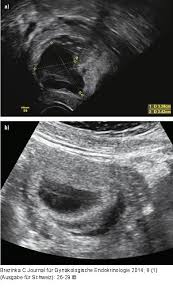

Abbildung 2a B Gyn Ultraschall